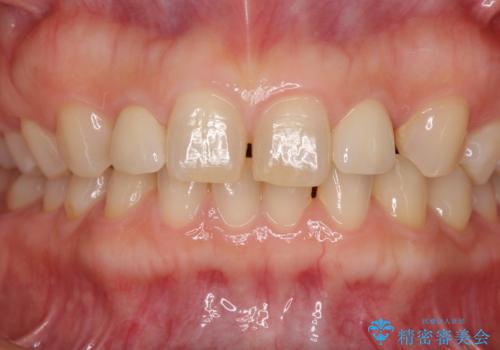

前歯の隙間や、周りの歯と色合いの違いなどはあまり気にしていらっしゃらなかったため、矮小歯の2歯を自然な大きさに仕上げました。

とても自然な歯が装着されたとのことで、患者様には大変満足していただきました。